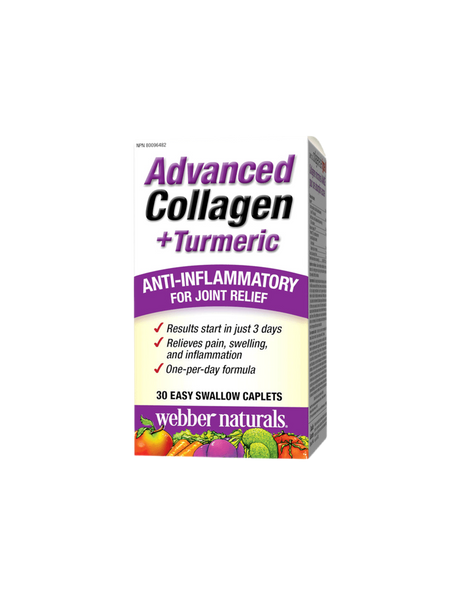

Любим!Ползвам от 2 години.Доволна съм от ефекта. Имах болки в тазобедрената става и започнах да приемам.Противовъзпалитилно е.Подпомага много сериозно имунната система. Повлия и на сърдечно съдовата система, от менопаузата вълни и ускорен пулс.Повлия и храносмилателните процеси.Много ползи!Благодаря!!!